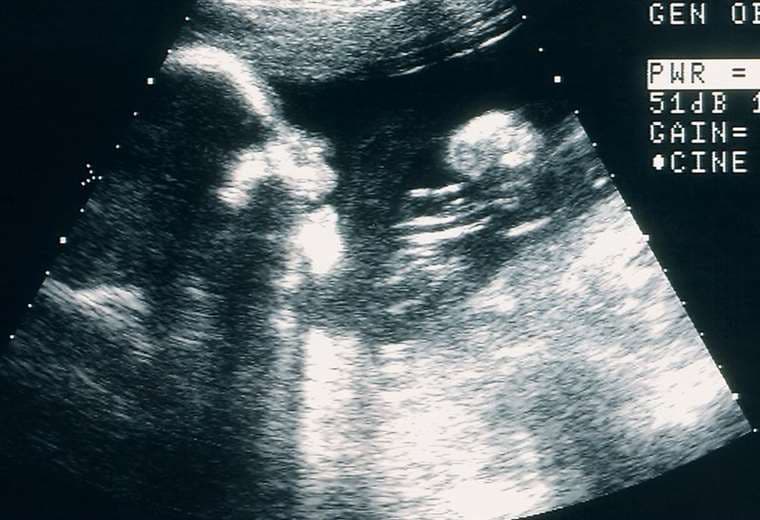

"Había ido al médico por otro tema y cuando le conté que estaba embarazada me hicieron una ecografía. Cuando no encontraron el latido, para mí fue un shock emocional. No había tenido pérdidas, no había ningún indicio de que algo iba mal", dice.